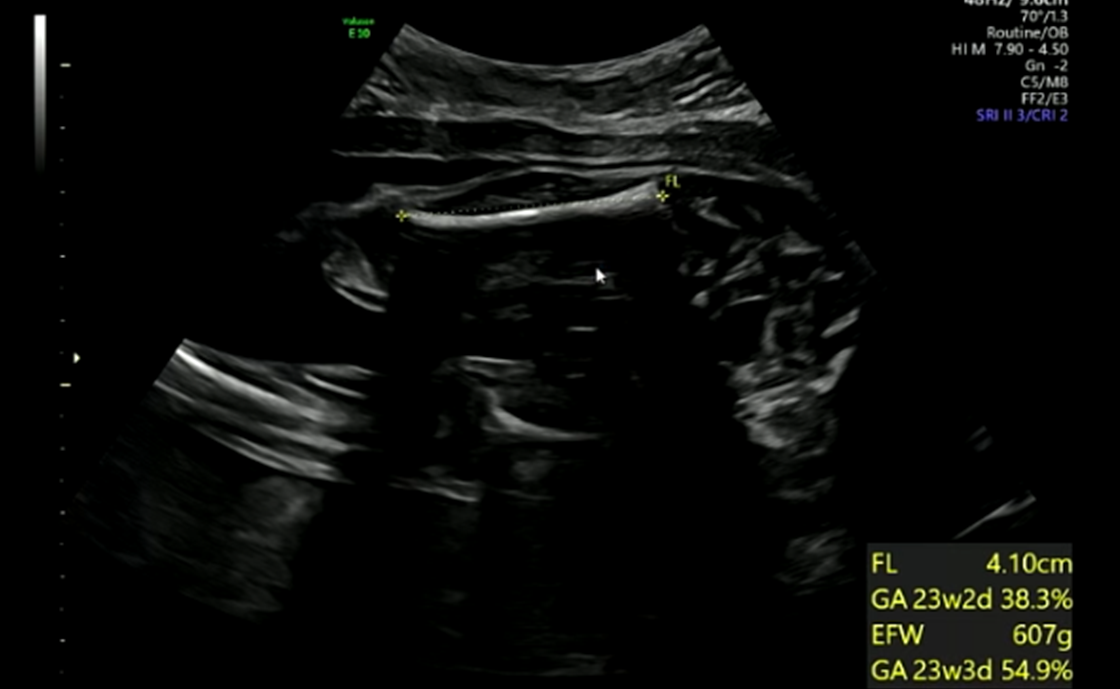

허벅지길이/몸무게

※ 초음파 용어 : FL : 허벅지 길이, EFW : 예상 몸무게